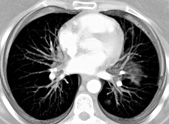

CT bei Krebsprävention und -erkrankung (Onkologie)

Mit der Mehrschicht-CT (MSCT) können wir durch schnelle Volumenaufnahmen mit hoher räumlicher Auflösung und geringer Dosis Tumorvorläufer bereits im Frühstadium erkennen.

Virtuelle Verfahren (etwa ein "Flug" durch den Dickdarm) machen Gewebeveränderungen sichtbar. Häufig müssen Kontrastmittel eingesetzt werden, z.B. bei Untersuchung von Leber, der Niere und der Lunge. Besonderen Einsatz erfährt die CT bei der Erfolgskontrolle therapeutischer onkologischer Eingriffe und bei der Nachsorge.